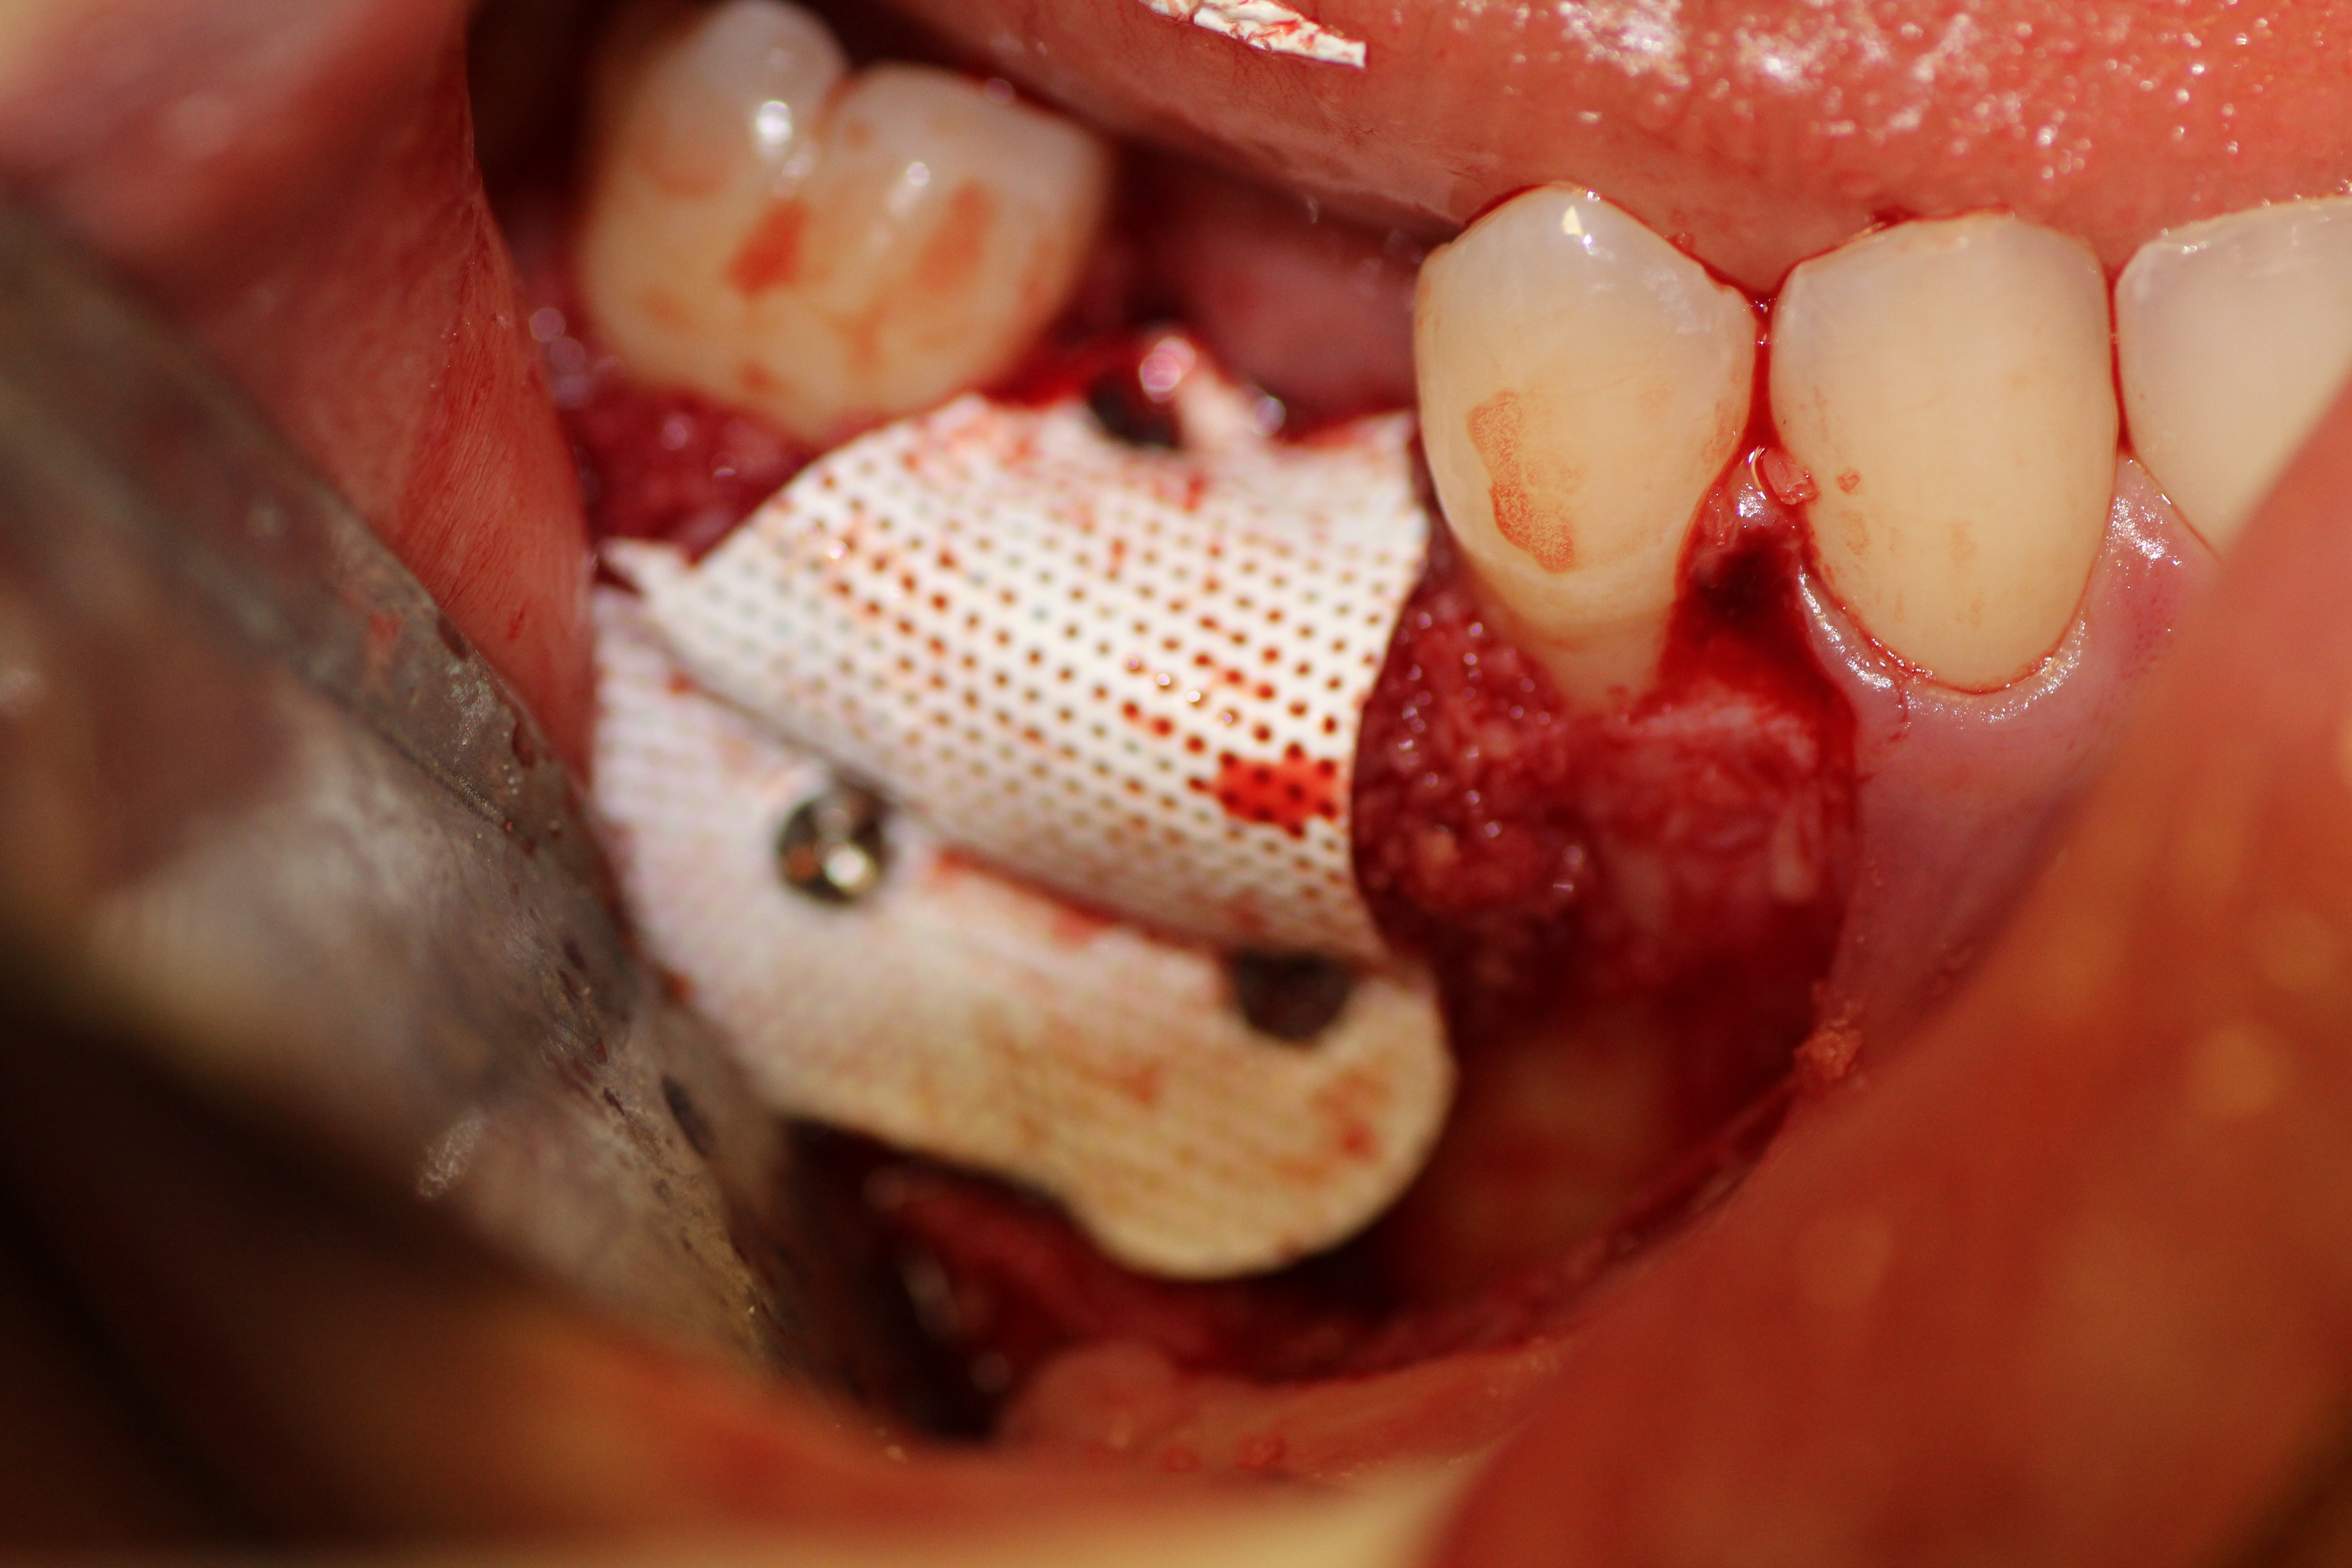

Immediate placement with bone guided regeneration.

- Implant in place with mental nerve isolated.

- Buccal plate decorticated.

- Bone graft in place.

- Bone graft stabilized with PFTE membrane and fixation sutured.